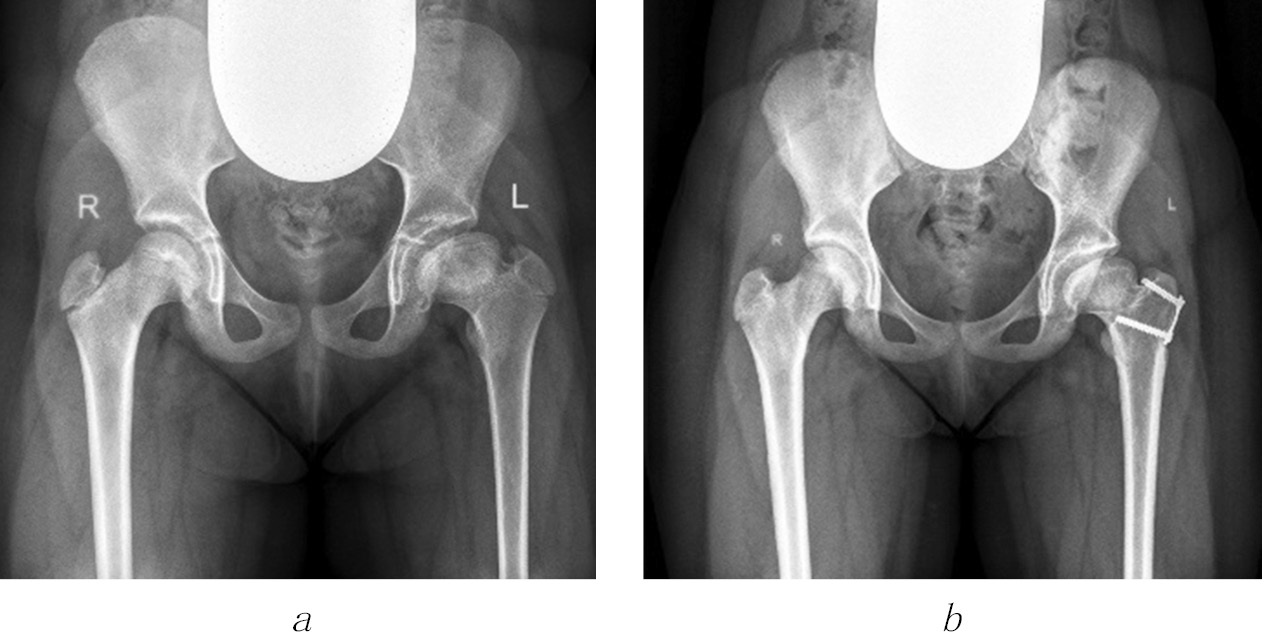

Fig. 1. Radiographs of patient U (7 years old) diagnosed with congenital dislocation of the right hip, condition after conservative treatment, and residual developmental hip dysplasia. Complications of aseptic necrosis of the femoral head include femoral neck shortening, formation of Kalamchi type II deformity, and high position of the greater trochanter: a, at 4 months old; b, at 1 year old; c, d, at 7 years old, before surgery; e, immediately after iliac pelvic osteotomy and trochanteric epiphysiodesis on the right